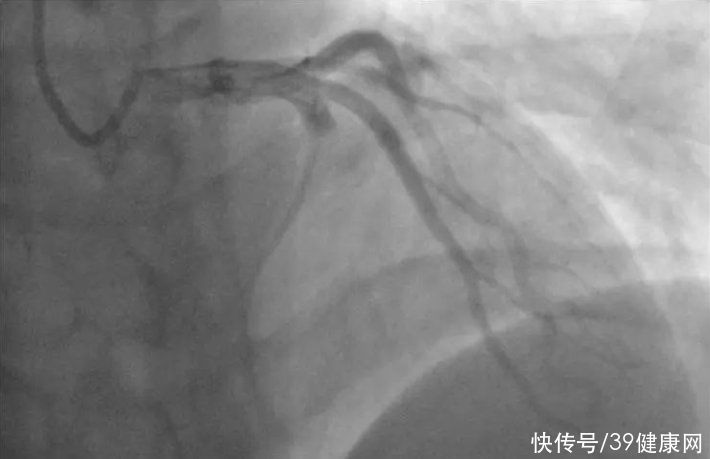

随后,医生给他进行了第二次心电图检查,提示ST段抬高明显,心肌损伤标志物也开始升高,术前的冠脉造影提示“血管严重堵塞”。为了挽救生命,医生立即做好手术准备。

随后小刘被紧急推入了介入导管室,经过1小时手术,医生抽出了大大小小共10块血栓,最大的一块把导管都堵了,只能反复抽吸。

同时,医生还使用抗凝药物进行溶栓,尽量将残存血栓解决干净。

术后造影提示,小刘的冠脉血流恢复情况良好。从确诊到手术结束,一共只花了1个小时。